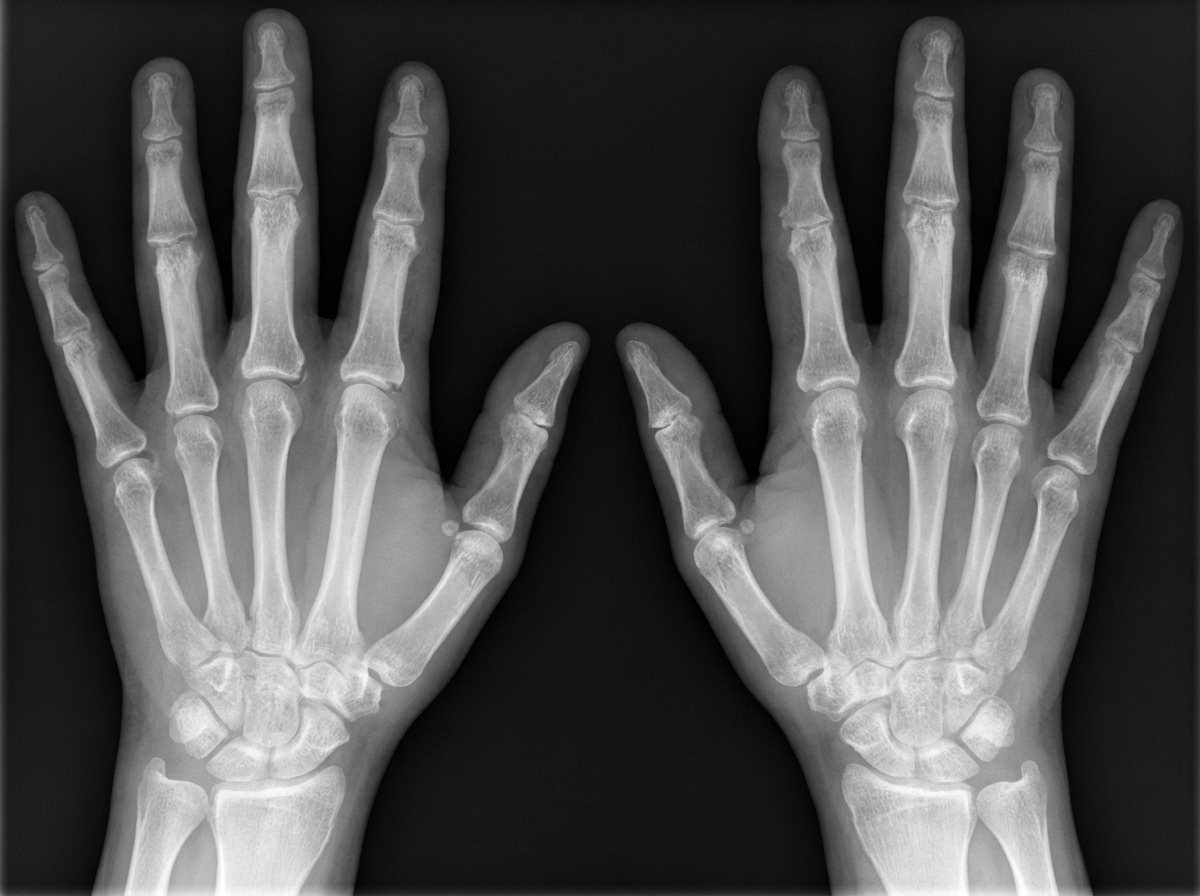

A 42-year-old woman comes to the physician because of an 8 month history of intermittent pain and stiffness in her hands and feet. She reports that these episodes occur about three times a month after she wakes up and last for approximately one hour. She often also experiences fever and myalgia on the days that these episodes occur. During these attacks, she takes ibuprofen for the pain, which provides good relief. She had her last attack 5 days ago. She is otherwise healthy and takes no medications. Her sister has systemic lupus erythematosus. Vital signs are within normal limits. Examination shows mild swelling and tenderness of the wrists and the proximal interphalangeal joints of both hands. The remainder of the examination shows no abnormalities. An x-ray of her hands is shown. Which of the following is the most appropriate pharmacotherapy?